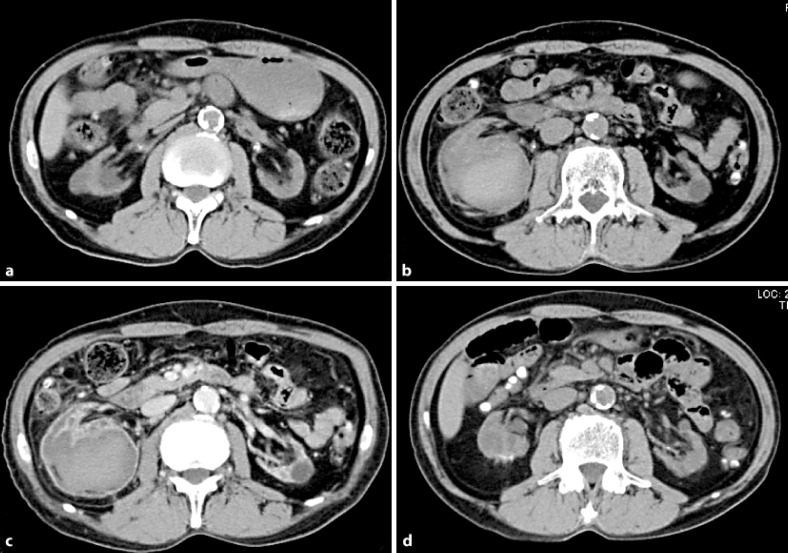

Dialysis patients have a tendency to bleed, and clinicians sometimes encounter cases with a significant amount of spontaneous hemorrhage. We herein report two cases of spontaneous renal hemorrhage in hemodialysis patients. CASE 1: A 70-year-old male who had received hemodialysis for 8 years presented with right abdominal pain. He had a history of renal failure due to diabetes mellitus. CT showed a right perirenal hemorrhage. Angiography revealed a right renal artery hemorrhage, and catheter embolization was performed. CASE 2: A 76-year-old male who had undergone 7 years of continuous ambulatory peritoneal dialysis and 1 year of hemodialysis presented with right abdominal pain. He had a history of renal failure due to IgA nephropathy. CT showed a right perirenal hemorrhage. He received a blood transfusion and was put on absolute bed rest. At 2 days after admission, his anemia was found to have improved.